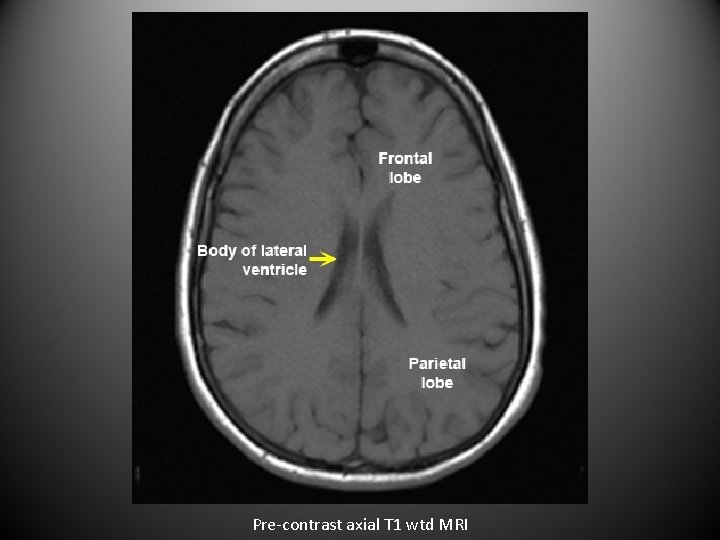

• For axial images you need to know the level. • The next set of images are axial sections of brain from top to bottom.

Pre-contrast axial T 1 wtd MRI